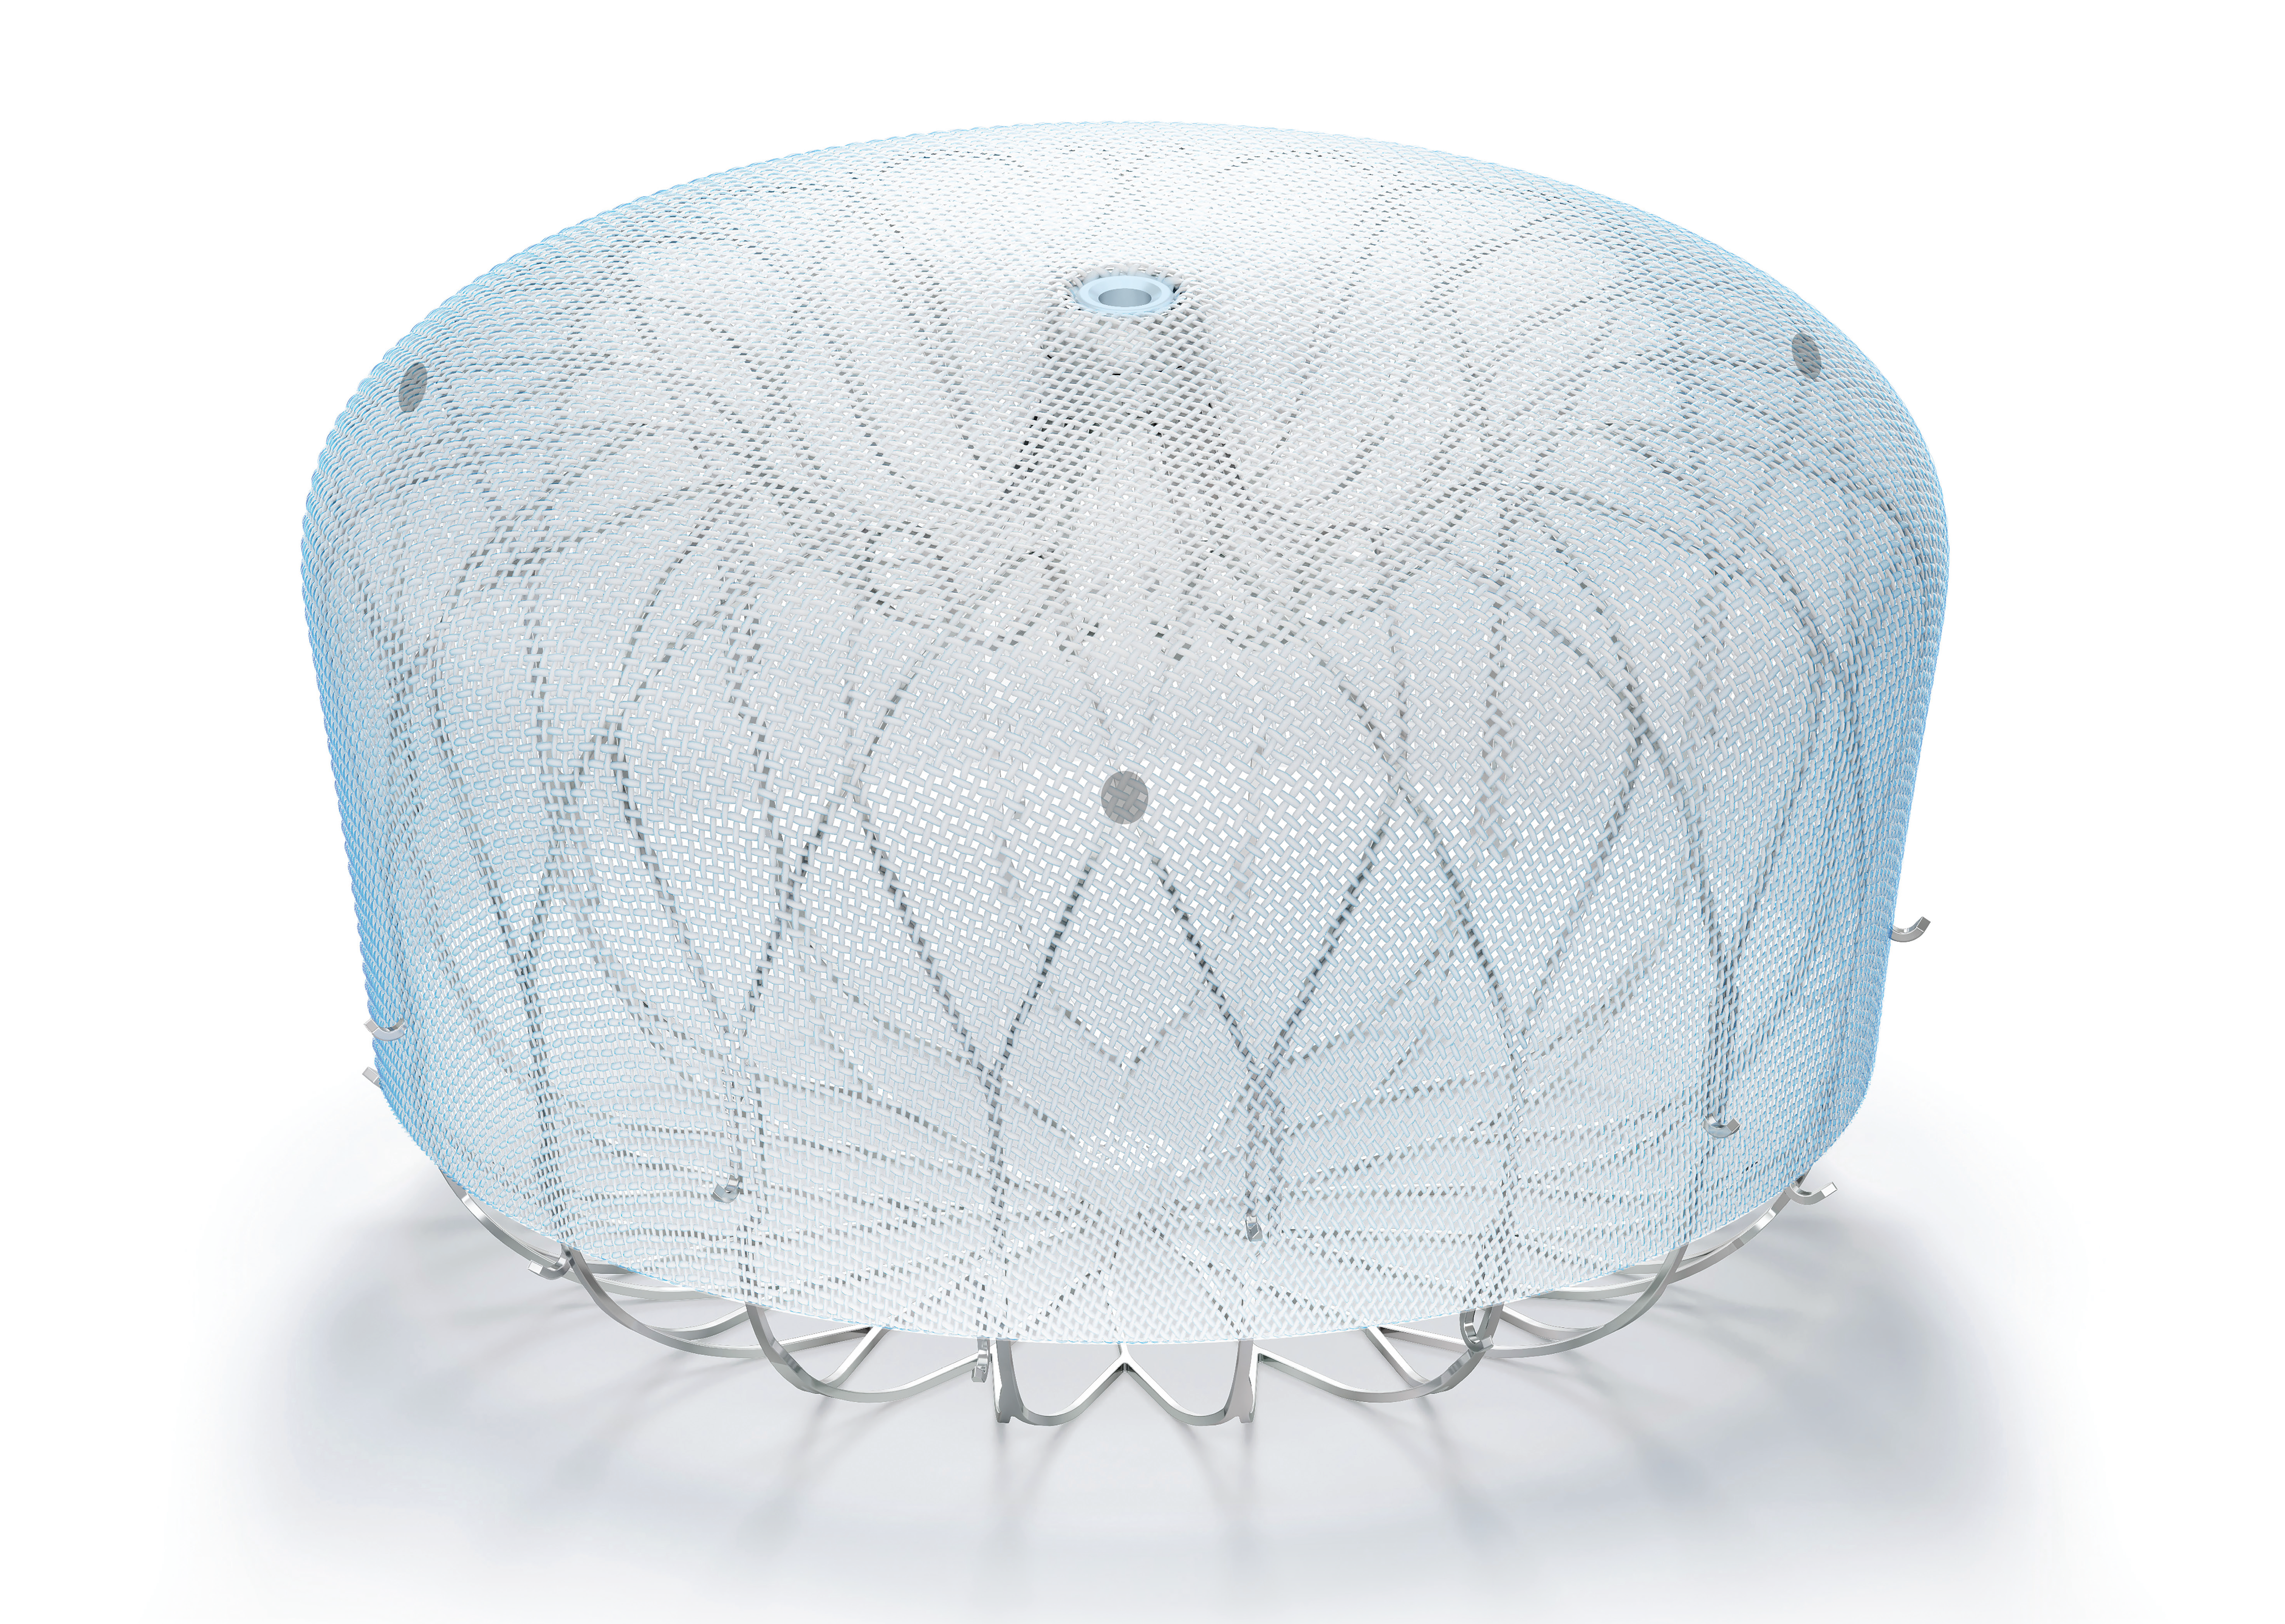

WATCHMAN FLX™ Pro LAAC Device

WATCHMAN FLX™ Pro is a Left Atrial Appendage Closure (LAAC) device, designed to reduce the risk of stroke in patients with non-valvular AF. Built on the proven performance of the WATCHMAN FLX™ device, the WATCHMAN FLX™ Pro device is optimized for healing.

WATCHMAN FLX™ LAAC Device

Learn about left atrial appendage closure (LAAC) procedure with WATCHMAN FLX™ and how it can help manage the risk of stroke for your patients with non-valvular AF.